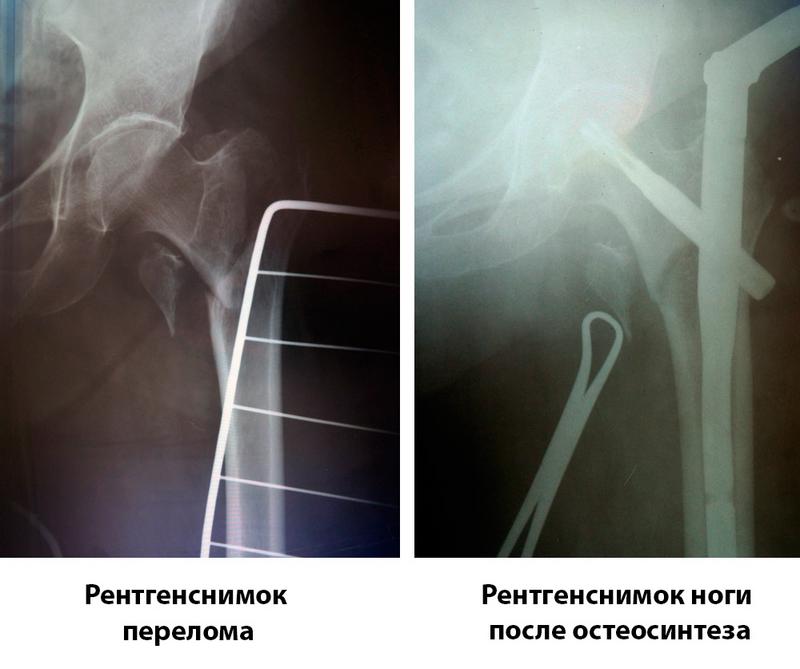

"В преклонном возрасте сращение костей без операции практически невозможно. Поэтому нашими специалистами широко применяются современная методика остеосинтеза. В данном случае для Лидии Карповны мы использовали специальный гамма-гвоздь (бедренный стержень). Он надежно фиксирует перелом даже в пораженной остеопорозом кости, но самое главное - пациентам не нужен гипс и длительный постельный режим. Уже через несколько дней после операции они могут вставать на ногу и без посторонней помощи ходить", - комментирует Ольга Богдан, заведующая отделением травматологии Запорожской областной больницы.

Важную роль в успешном исходе таких операций играет специальное оборудование, которое травматологи ЗОКБ используют во время установки бедренных стержней – ЭОП (электронно-оптический преобразователь). Это мобильный рентген-аппарат, который дает возможность делать рентген-снимки прямо в операционной в режиме реального времени и сразу же просматривать их на мониторе. Такой аппарат - "глаза хирурга", он позволяет надежно скрепить все отломки кости без больших разрезов, не травмируя пациента дополнительно. Это значительно уменьшает кровопотери для пациента и дает шанс восстановиться в разы быстрее.

Благодаря многолетнему опыту специалистов отделения травматологии ЗОКБ, операция пациентки прошла успешно. Совершенное владение методикой остеосинтеза и применение самых современных фиксаторов позволило врачам областной больницы успешно справиться с таким серьезным переломом. Спустя две недели лечения в Запорожской облбольнице Лидия Карповна выписывается домой.